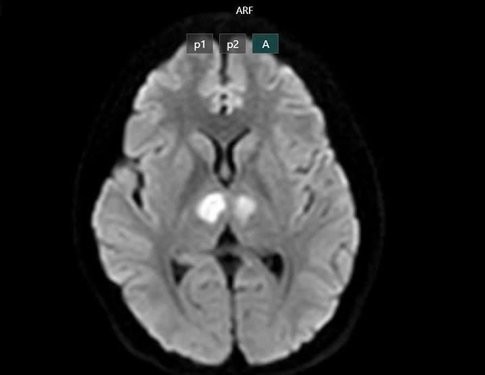

Hệ lụy tổn thương não do nhiễm độc chất cấm sau sử dụng sản phẩm giảm cân không rõ nguồn gốc .Ảnh: BỘ Y TẾ

Cụ thể, một cô gái 21 tuổi ở Hà Nội hiện bị tổn thương não nặng (đang còn điều trị) sau khi sử dụng sản phẩm sức khỏe mua trên TikTok dẫn đến nhiễm độc Sibutramine. Cô vốn khỏe mạnh, đang dùng sản phẩm tự mua này gần một tháng (bao bì hoàn toàn bằng tiếng nước ngoài, không rõ là thuốc hay thực phẩm chức năng) thì đột ngột bất tỉnh, không sốt, không co giật. Kết quả MRI cho thấy tổn thương vùng đồi thị hai bên não. Hay một phụ nữ 37 tuổi đi cấp cứu sau khi sử dụng cà phê giảm cân; uống đến lần thứ 4 thì bị khó thở, lạnh toát, háo nước, hạ thân nhiệt đột ngột; kết quả xét nghiệm xác định sản phẩm chứa Sibutramine.